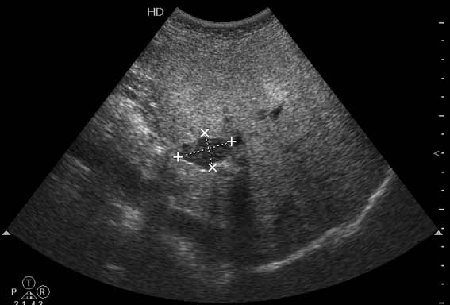

В печени выявлен гипоэхогенный очаг неокруглой формы, аваскулярный при цветовой доплерографии.

Простая и одновременно "сложная" задачка. По УЗИ; явный стеатоз печёночной паренхимы (теперь ключевые слова); на ФОНЕ СТЕАТОЗА определяется гипоэхогенное образование. Варианты? Очаговое образование; и менее вероятно участок гипостеатоза (но не похоже, есть чёткие границе, + не та локализация).

Вывод: надо иметь ввиду, что эхогенность это относительное понятие, эхогенность гемангиомы может изменятся при изменении положения обследуемого пациента (см. прикреплённую статью); не надо забывать что эхогенность образование это понятие относительное, т.е. относительно окружающей паренхимы печени! При стеатозе, гемангиома может выглядеть гипоэхогенно по отношению к гиперэхогенной паренхиме окружающей печени. И главное, есть сомнение-заказываем таргетное мультифазовое КТ.